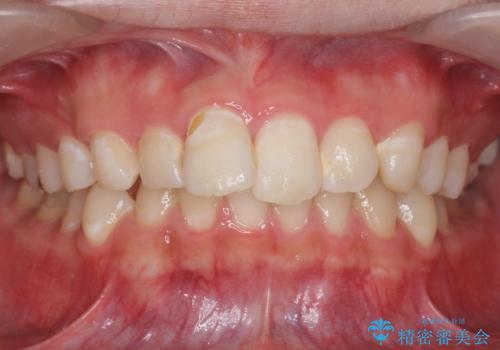

[ 再生治療・歯周外科・小矯正・セラミック補綴 ] 前歯の歯周病治療

担当医 大元洋佑

![[ 再生治療・歯周外科・小矯正・セラミック補綴 ] 前歯の歯周病治療の症例 治療前](https://seimitsushinbi.jp/wp/wp-content/uploads/2022/12/83065c2454a29ed71cf190e15a6106f4-500x350.jpg?v=1671673398)